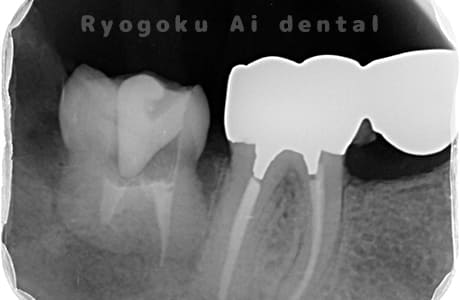

Case03

- 重度カリエス、慢性根尖性歯周炎

- 治療内容

- 自家歯牙移植

- 治療費用

- 220,000円

他院で右下の根の治療を行い、セラミックを被せる説明をされていたが、根の治療が終わらないため転院された患者さんです。隣の親知らずの抜歯の必要性と、根の治療を行なっている歯牙の予後が悪いため、移植治療を提案し、右下の親知らずの抜歯と同時に、右下の奥歯(7番)への移植治療を行いました。被せ物を行う必要もなく、順調に経過してます。